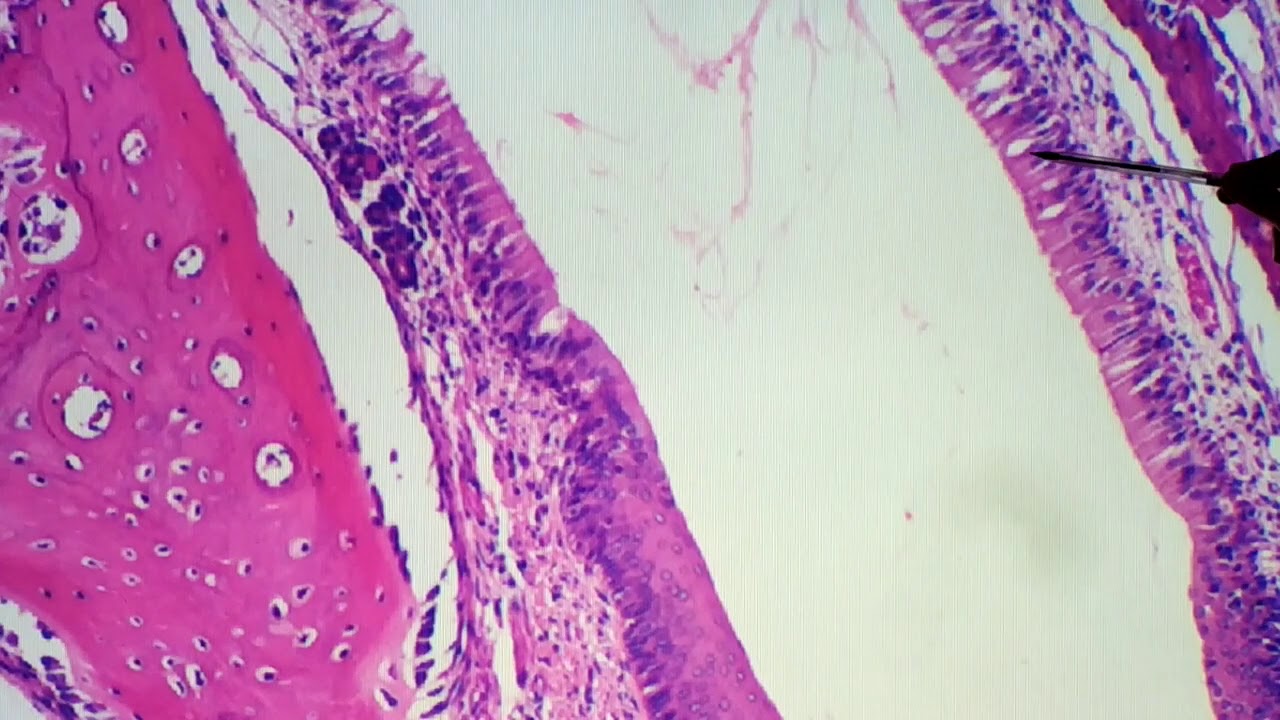

observar uma região mais próxima à região da língua nessa região mais próxima à região da língua que dá epiglote nós vamos ter um tecido epitelial estratificado pavimentou zhu nunca utilizado já na região sul é posterior nós vamos ter um epitélio respiratório que o epitélio estratificado a desculpa é o arquiteto pseudo estratificado observem que eu tenho exatamente a zona de transição do império estratificar no telecine ficado pavimentou nunca utilizado para o epitélio e seu do estratificado o que é essa exatamente na zona de transição entre os dois cemitérios recebem que a região transição abrupta então nós

temos um tipo de critério e posteriormente nós vamos ter um outro tipo de pele completamente diferente aqui nós vamos ter a região da lâmina própria que é composto por tecido conjuntivo isso não muda de lado nós vamos ter então as glândulas mais uma vez glândulas sério mucosas e aqui como a gente sabe tecido cartilaginoso nesse caso aqui da cartilagem nesse caso a cnaa da cartilagem nós vamos ter uma cartilagem elástica como eu sei que essa cartilagem na cartilagem elástica pela coloração então a gente consegue observar que nós vamos ter é que essa cartilagem ela vai